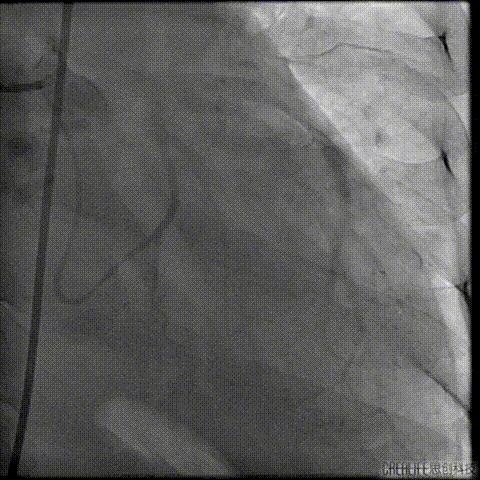

预扩主动脉瓣

NUMED 25mm*40球囊

180/分起搏下预扩主动脉瓣

左冠血流受到影响

予ECOM支持

扩瓣结束后,患者出现心跳骤停

予胸外按压,并予ECOM支持后

患者恢复自主心率